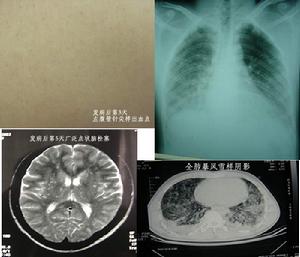

發生率約75%。開始於缺氧導致的呼吸急促及隨後的過度換氣,紫紺有時不會出現,但有時可能成為FES的早期體徵。涉及肺的FES病人大部分PaO2水平低於6.67kPa,如果肺的條件惡化,就可能合併呼吸困難和代謝性酸中毒。部分病人有咯血。胸部X線片示兩肺大塊斑片狀陰影,稱之為“暴風雪樣”改變,尤其在肺的上中部多見。

脂肪栓塞綜合徵--X線1呼吸支持療法不完全型或部分症候群:可以鼻管或面罩給氧,使氧分壓維持在9.3-10.7kPa(70-80mmHg)以上即可,創傷後3-5天內應定時血氣分析和胸部X線檢查。